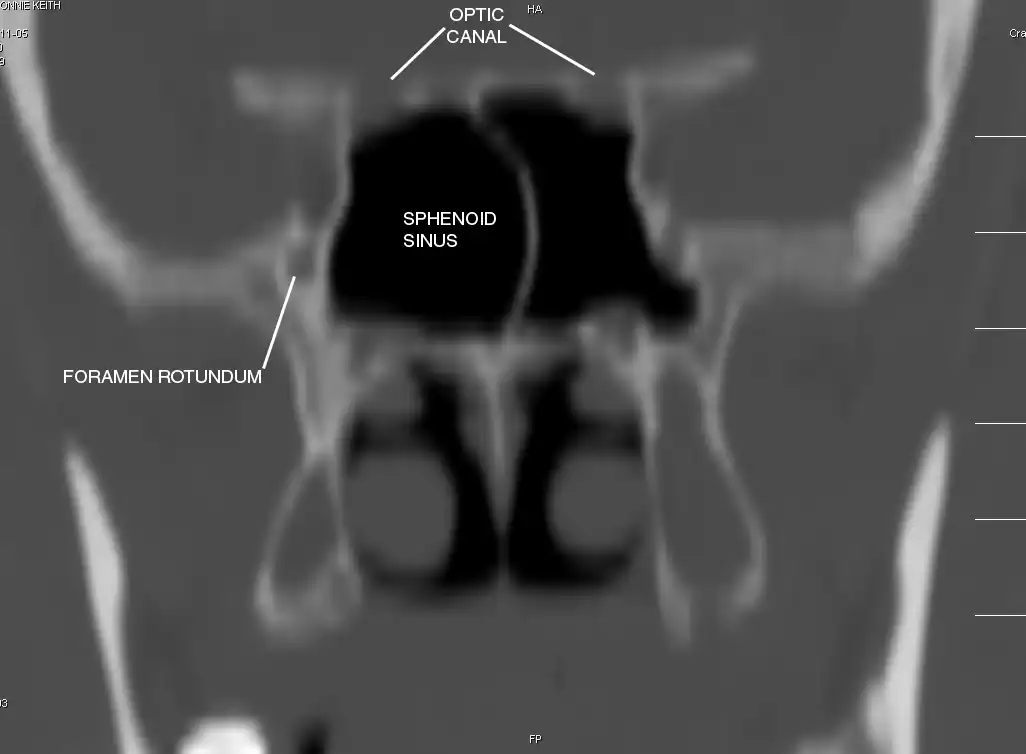

Sphenoid Sinus has 12 close structures: II, III, IV, V1, V2, VI, Vidian Nerve, Carotid artery, Brain, Dura, Pituitary.

- II = Optic Nerve: 25-50% with bony dehiscence into sphenoid sinus.

- V2 = Maxillary division, Trigeminal Nerve: exits foramen rotundum, superomedial to V3's foramen ovale.